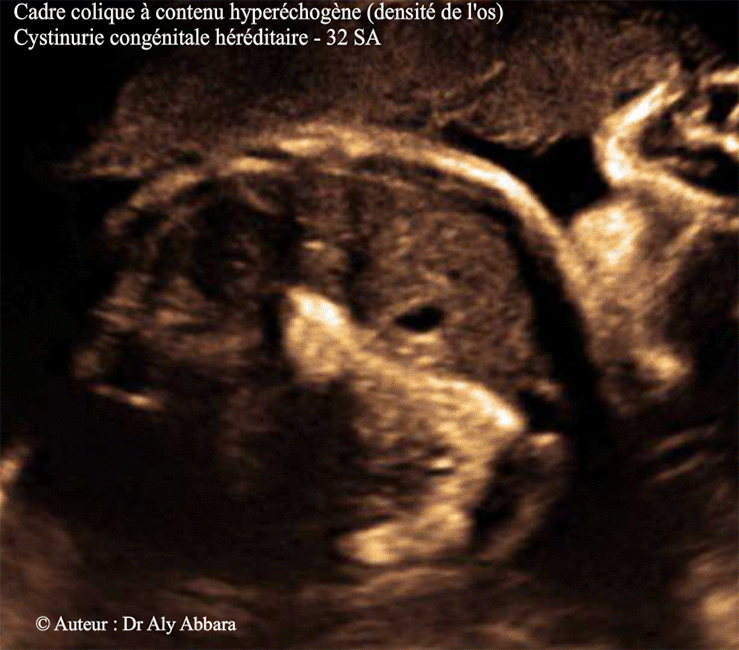

Colon (cadre colique) hyper-échogène - cystinurie hériditaire

Côlon à contenu hyperéchogène

Grossesse de 32 SA

Cystinurie héréditaire

Images échographiques montrant une grossesse de 32 SA caractérisée par la présence d'un côlon à contenu très hyperéchogène (échographiquement, de la même densité de l'os). Cette hyperéchogénicité est identifiable dans l'ensemble du cadre colique, y compris la région rectale, sans élagissement du diamètre du côlon, ni de modification de la paroi colique et enfin l'intestin grêle d'aspect normal.

Il s'agit d'un signe échographique fœtal souvent caractéristique de la cystinurie, maladie héréditaire autosomique

récessive.

• La maladie se manifeste in utero par la mise en évidence lors des échographies anténatales d'une hyperéchogénicité du contenu du côlon fœtal sans modification de son calibre ni de sa paroi, puis des anses grêles normaux.

La déglution fœtale du liquide amniotique et la non absorption de la cystine et les trois autres acides aminés au niveau l'intestin grêle entraînent leur accumulation dans le côlon (à partir de de la 22e SA, âge de la fermeture du sphincter anal) ; ce sont les dépôts de cristaux de cystine et d'autres acides aminés dans le méconium colique qui donnent au côlon sont aspect hyperéchogène sur les échographies anténatales.

L'image du côlon hyperéchogène est typiquement colique, et ne prête pas à la confusion avec l'intestin grêle hyperéchogène.